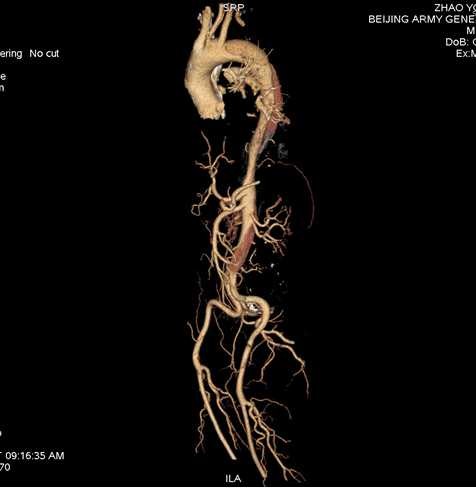

左图为A型主动脉夹层累及全主动脉;右图为B型夹层累及降主动脉以远